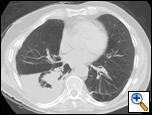

Although surgical management of patients with severe flail chest is at present controversial, we think that surgical stabilization is strongly indicated in specific clinical situations. The effectiveness and the ideal timing of chest wall stabilization in patients on mechanical ventilation is related to the degree of the pulmonary parenchymal damage [7,8]. The presence of extensive pulmonary contusion (Figure 1) is a relative contraindication to surgical stabilization. These patients require prolonged ventilation, and an early surgical stabilization would not provide benefit [7,8]. However, a surgical procedure can be proposed if the patient fails to wean from the ventilator once a partial resolution of pulmonary contusion is achieved [9,10].

In patients with isolated blunt chest trauma who have severe flail chest without significant pulmonary contusion, prolonged internal pneumatic stabilization is not suitable because of the risk of ventilator-related infectious complications. Moreover, mechanical ventilation is not always successful in preventing chest wall deformities that may result in a subsequent respiratory restrictive dysfunction [10,11]. In patients with mild or no pulmonary contusions (Figure 2), early surgical stabilization (within few days of internal pneumatic stabilization) may result in shorter intensive care unit stay with lower morbidity and prevention of pulmonary restrictive complications resulting in working incapacity [9].